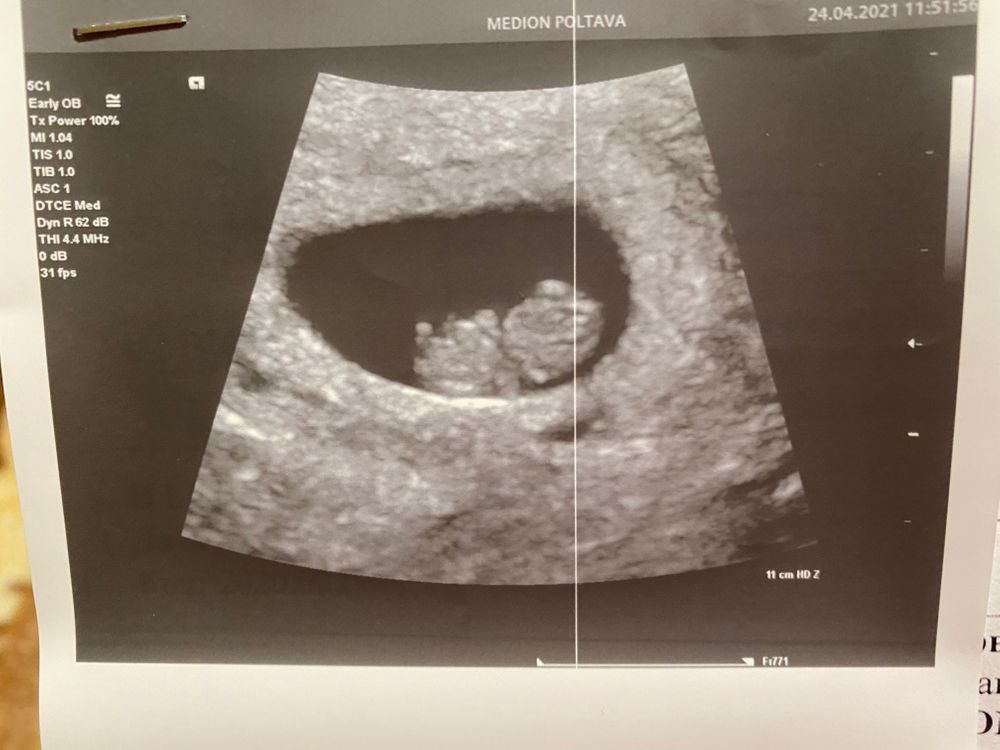

Узи 8+1

Наши будни, наши неделькиДелала ещё в 6+3, решила посмотреть динамику, и у нас все хорошо ☺️

КТР 1.43

ПЯ 4.53

растем 🥳🥳🥳